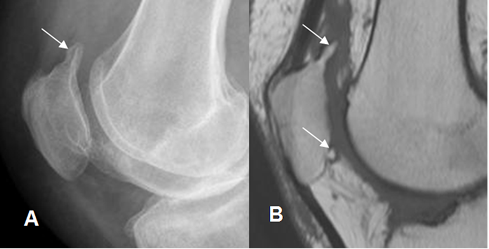

Fig 7. Artropatía degenerativa en rodilla.

A: Rx AP y B: RM coronal en T1. Hallazgos típicos con formación de osteofitos

(Flechas delgadas), disminución del espacio articular y erosión del hueso subcondral.

(Flechas gruesas).